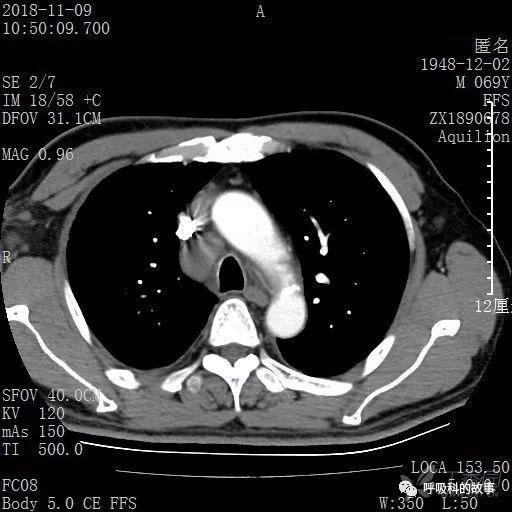

胸部增强CT示右肺门占位伴远端阻塞性肺炎,纵膈、右肺门、右侧颈根部、右侧腋下及肝门部肿大淋巴结。两侧胸腔少量积液。

纵隔窗的增强CT

患者于2018年12月初又到了另一家大医院,做了PET检查和气管镜检查,PET图片和报告:右下肺病灶在增大,PET呈现高摄取率,SUV最大达11.